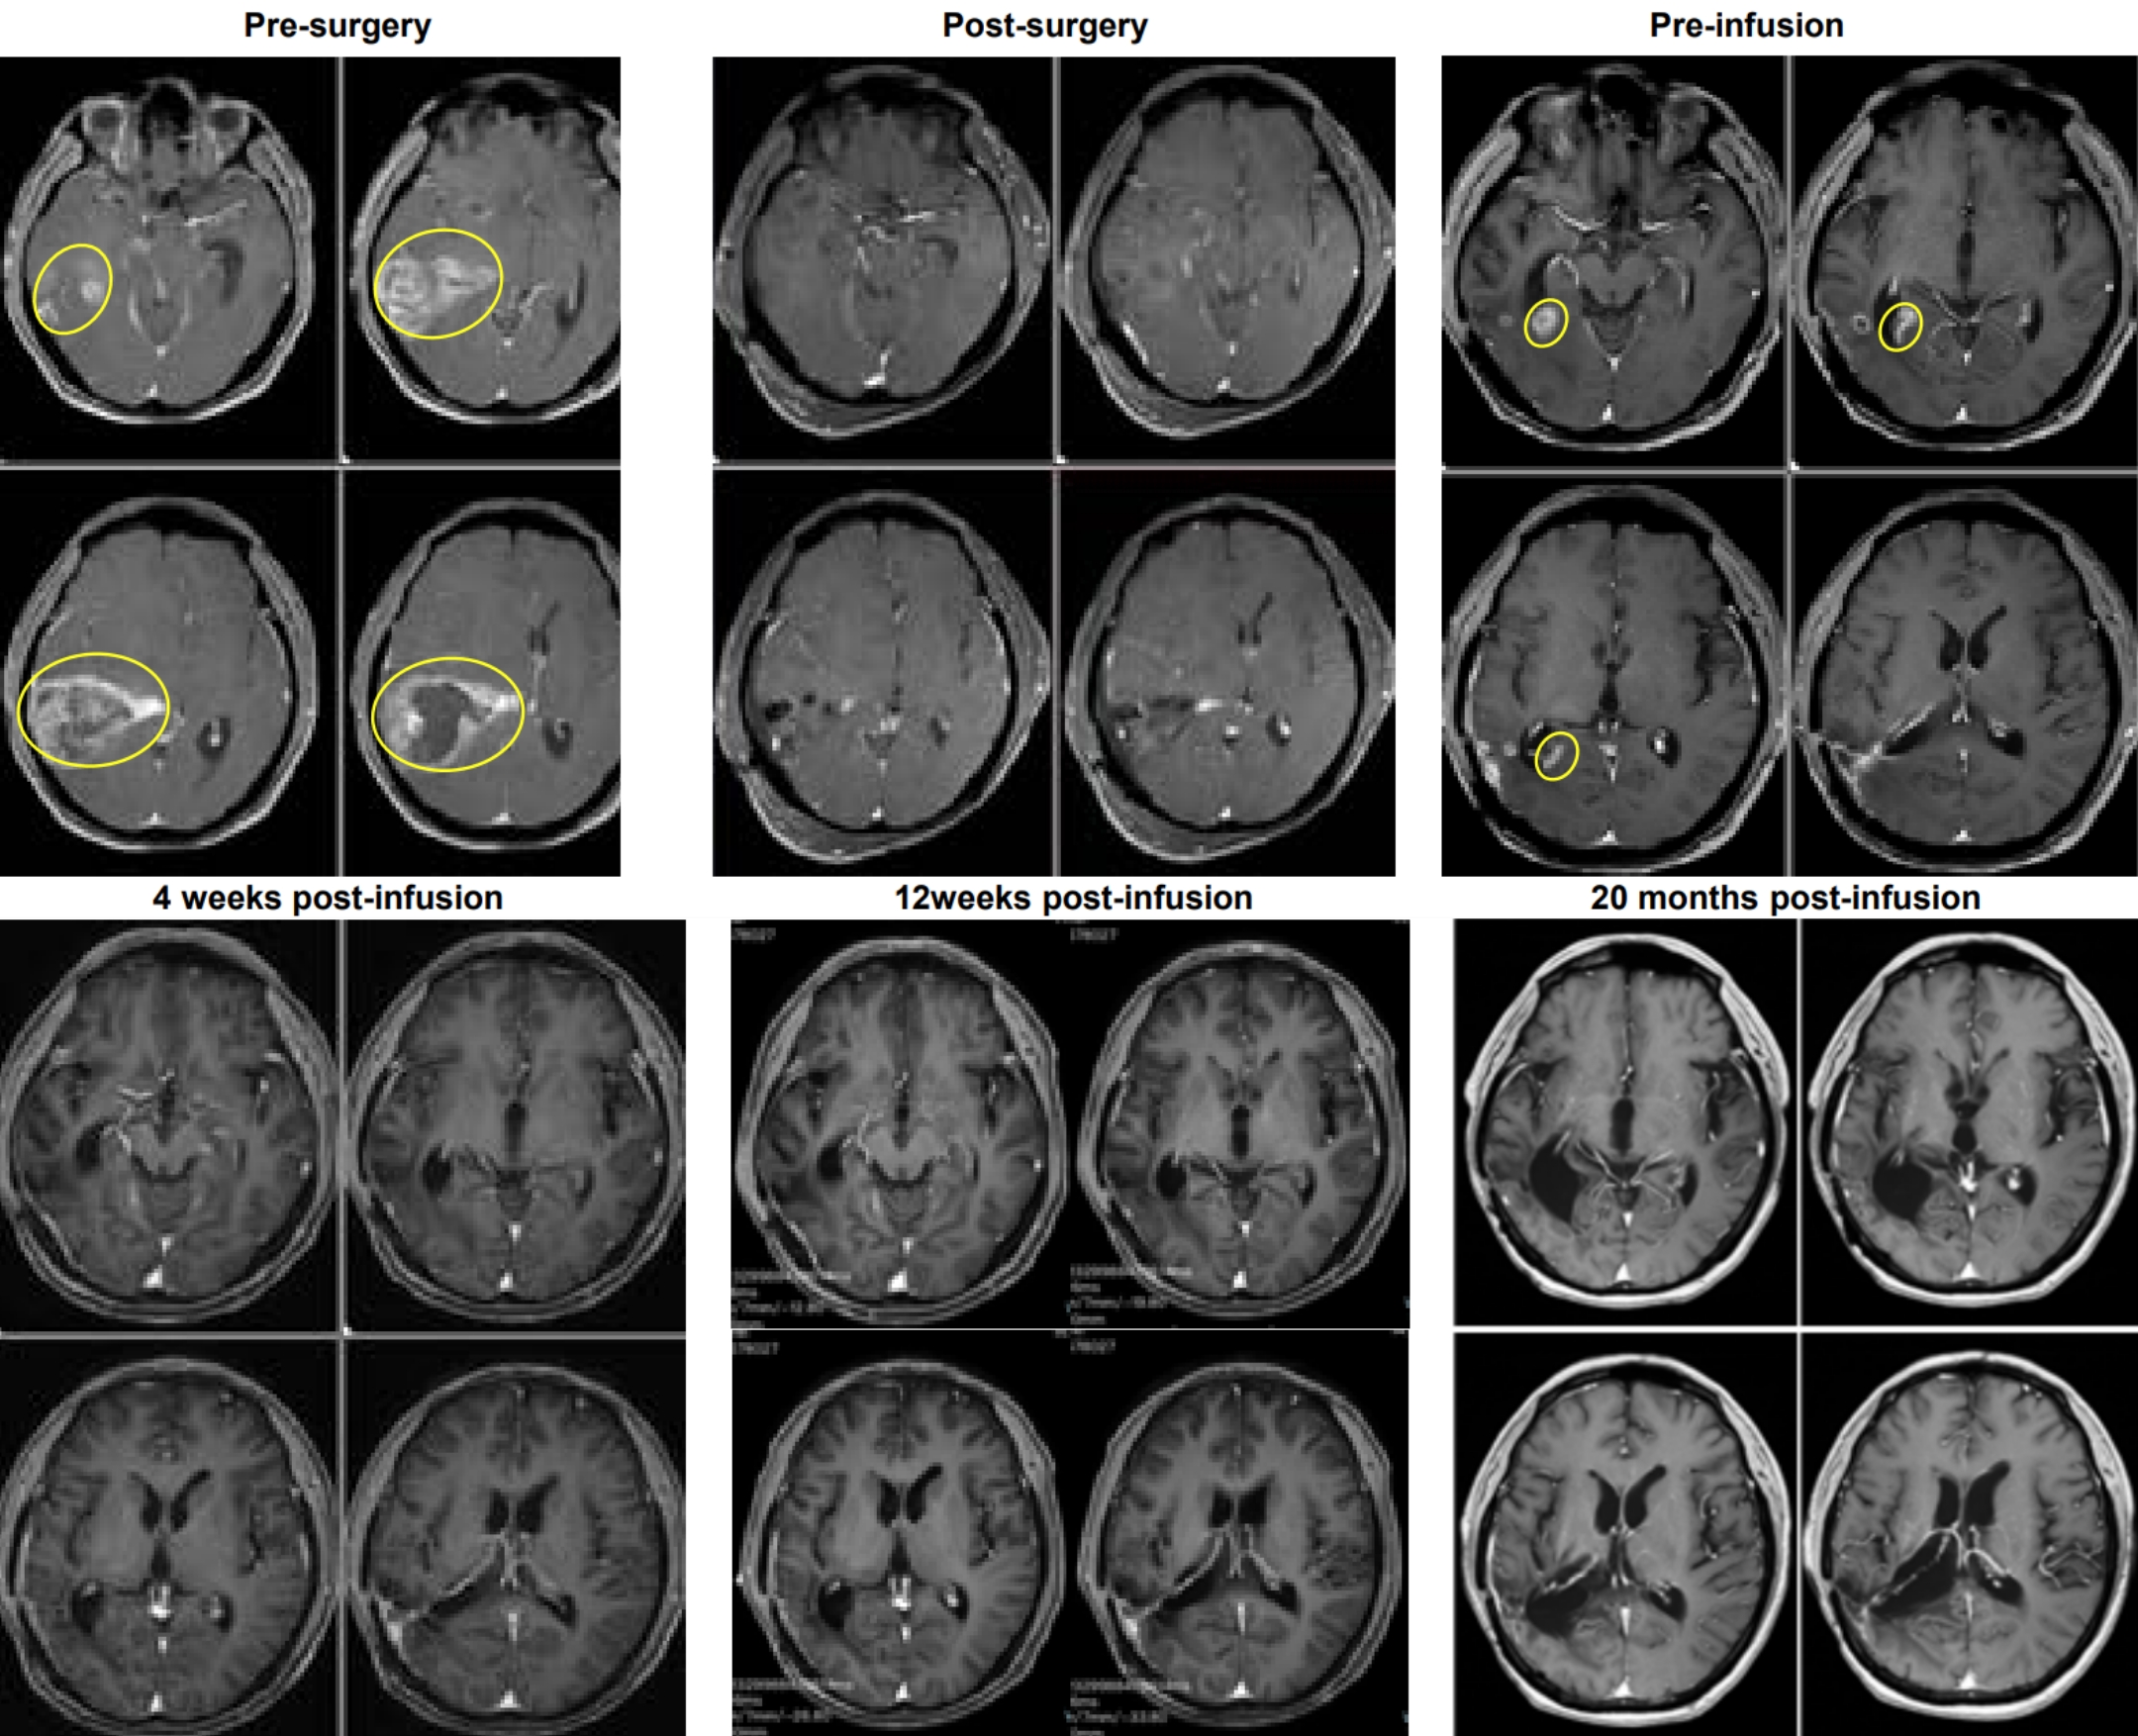

In desperation, he enrolled in a clinical trial for a novel TIL therapy. The results were astounding: just 4 weeks after the TIL cell infusion, imaging examinations showed the tumor in his brain had been completely eliminated, achieving a complete response, and he has remained tumor-free for over 20 months.

Just 4 weeks after the TIL cell infusion, imaging examinations on January 8, 2024, revealed that the tumor in Mr. W’s brain had been completely eliminated.

Even more remarkably, as of October 2025, the patient has maintained a tumor-free survival for over 1.8 years (calculated at the time of the news release, this is over 20 months), regaining a normal life.

This case sets a new survival record for recurrent glioblastoma and provides crucial clinical evidence for the treatment strategy of “early tissue sampling, TIL reinfusion upon recurrence.”